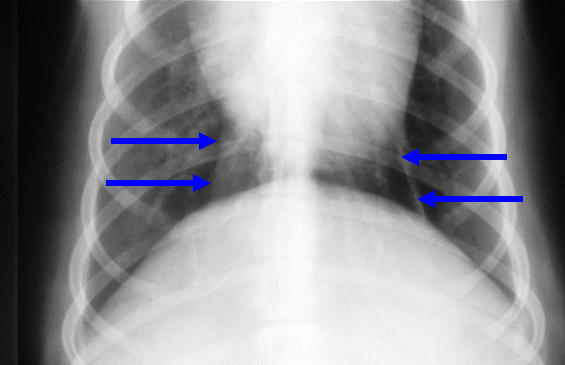

What can be seen here?

Caudal mediastinum

Reflection of pleura – represents the left part of caudal mediastinum – its not actually in midline, its slightly over to the left – if increased opacity in this caudal mediastinum, this is where increase will be – if its more midline opacity, more likely to be right lung lobe.